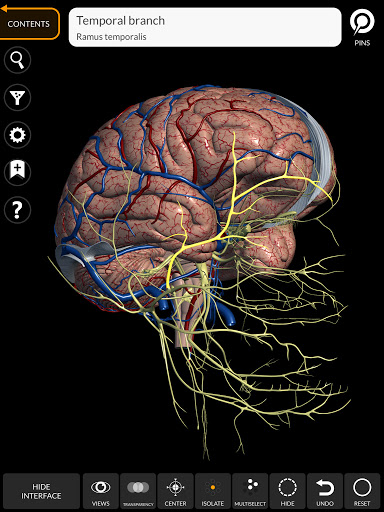

"Anatomy 3D Atlas" дозволяє легко та інтерактивно вивчати анатомію людини.

Завдяки простому та інтуїтивно зрозумілому інтерфейсу можна спостерігати кожну анатомічну структуру під будь-яким кутом.

Анатомічні 3D-моделі особливо деталізовані та мають текстури з роздільною здатністю до 4k.

Поділ за регіонами та попередньо визначені види полегшують спостереження та вивчення окремих частин або груп систем і зв’язків між різними органами.

• Нервова система